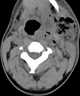

Neck infection